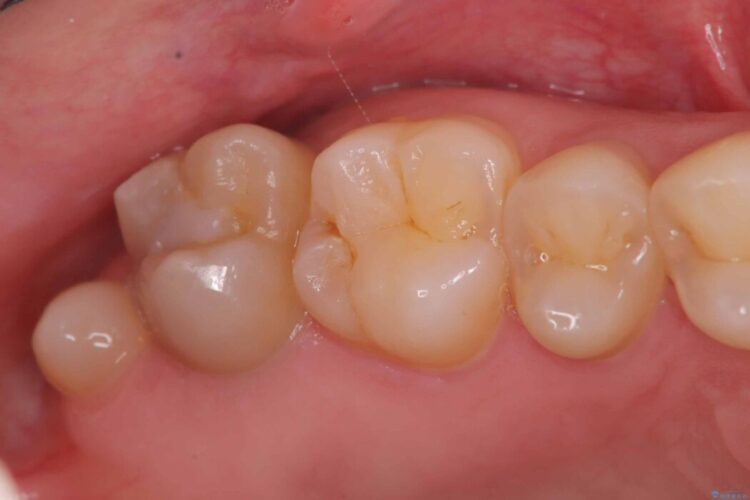

自然な見た目のセラミックインレーで精密に修復

自然な見た目のセラミックインレーで精密に修復 ビフォー 自然な見た目のセラミックインレーで精密に修復 アフター

右上5番に小さな穴があるとご相談にいらした患者様です。